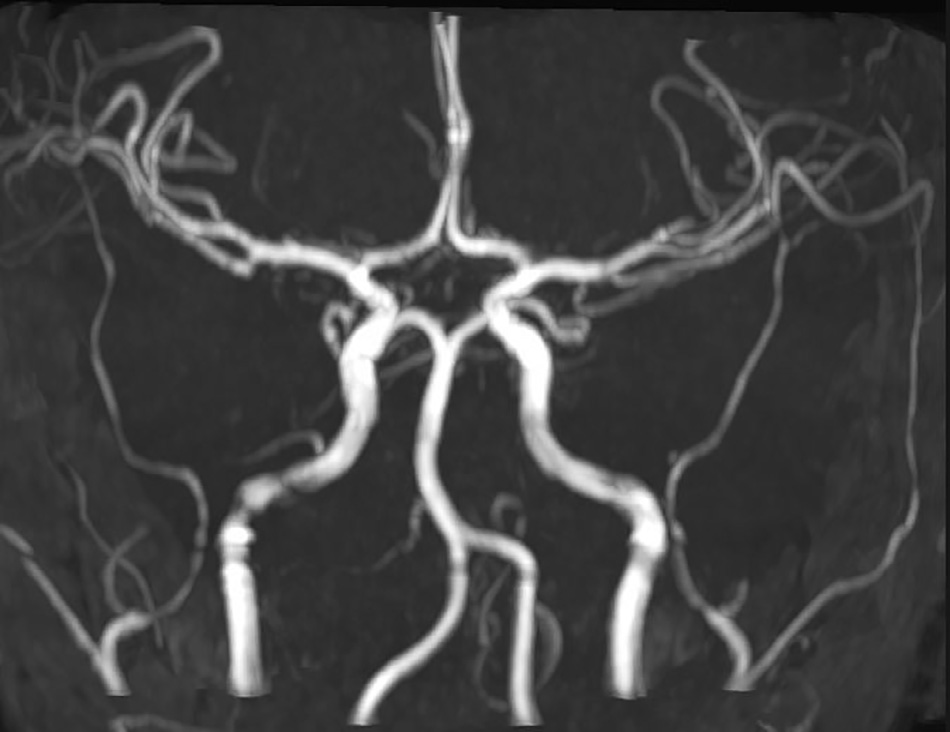

图2